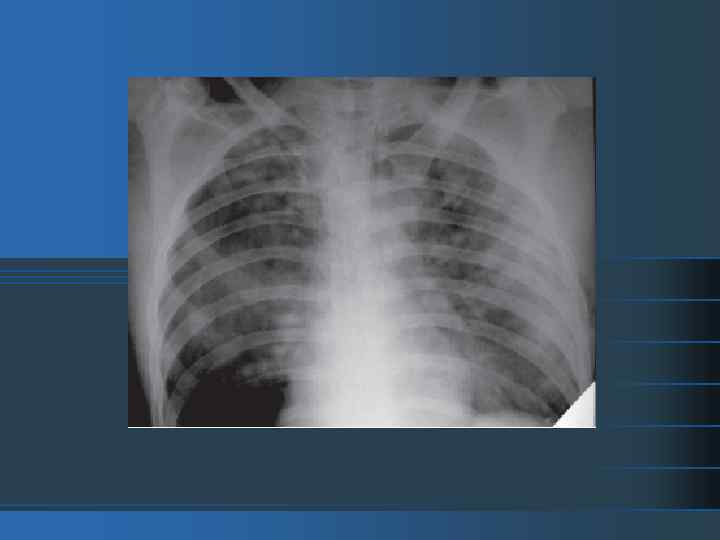

Острый РДСВ острое начало; 2) двусторонняя легочная инфильтрация (билатеральные легочные инфильтраты на рентгенограмме); 3) происхождение отёка: дыхательную недостаточность нельзя объяснить сердечной недостаточностью или перегрузкой жидкостью. 4) гипоксемия, рефрактерная к оксигенотерапии: легкая: Pa. O 2/Fi. O 2 =< 300 при ПДКВ или CPAP >= 5 см водн. ст. средней тяжести: Pa. O 2/Fi. O 2 =< 200 1) тяжелая: Pa. O 2/Fi. O 2 =< 100 Отличие СОПЛ от РДСВ в степени гипоксемии, выраженной в форме отношения Ра. О 2 Fi. O 2; при СОПЛ Ра. О 2 Fi. O 2 < 300, при РДСВ < 200 мм рт. Ст. . 1)

Рентгенологическая картина «шокового легкого» сравнивается со «снежной бурей» - мозаичная структура, состоящая из зон ателектазов и отека.